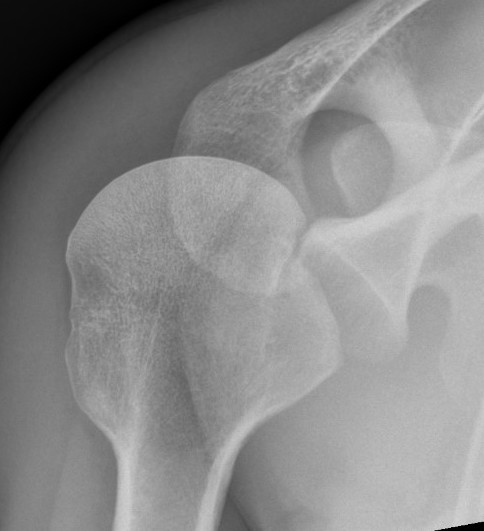

AP Xray

Abnormal overlap of humeral head on glenoid

Light-bulb sign - globular head secondary to internal rotation of the humeral head

Vacant Glenoid Cavity - > 6 mm space between humeral head and anterior rim of glenoid